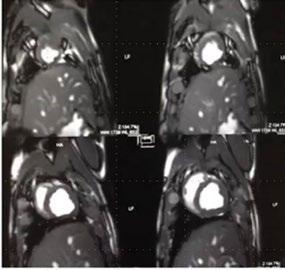

Cardiac screening for proactive health surveillance is firmly on the radar for all sporting organisations. This is not only to identify undetected anomalies that could put life and health at risk, but also to monitor for the onset of coronary artery disease as players age. Indeed, from youth teams to the veteran professional footballer, anyone undertaking vigorous training and competitive matches is regulated to receive cardiology profiling every 2 years1

The imaging tool that has traditionally been used is ultrasound echocardiography, looking at the structure of the heart at rest and during stress exercise. Now, and increasingly, the structure and functionality of the heart is examined via the latest generation in MRI.

For example, new developments have accelerated the examination time for cardiac MRI, with fewer patient breath holds needed to deliver much more detailed, richer image outputs that give another level of screening and profiling of the more subtle presentations of cardiac anatomy.

Fig 1: Next generation MRI is being used to gather data on brain tissue volumes Dr. Steve McNally

From this season at Manchester United Football Club, we have started to gather data by using MRI (see fig 1) to measure volumes of brain tissue in specific areas, to monitor for a decrease in volumes over time. If the volumes become unusual or deviate from the norms that we would expect, it may help us identify early changes of CTE that need closer monitoring. This is a new, long-term data gathering study in our cohort of players that has been facilitated with the new next generation MRI3 now in place at our medical centre.